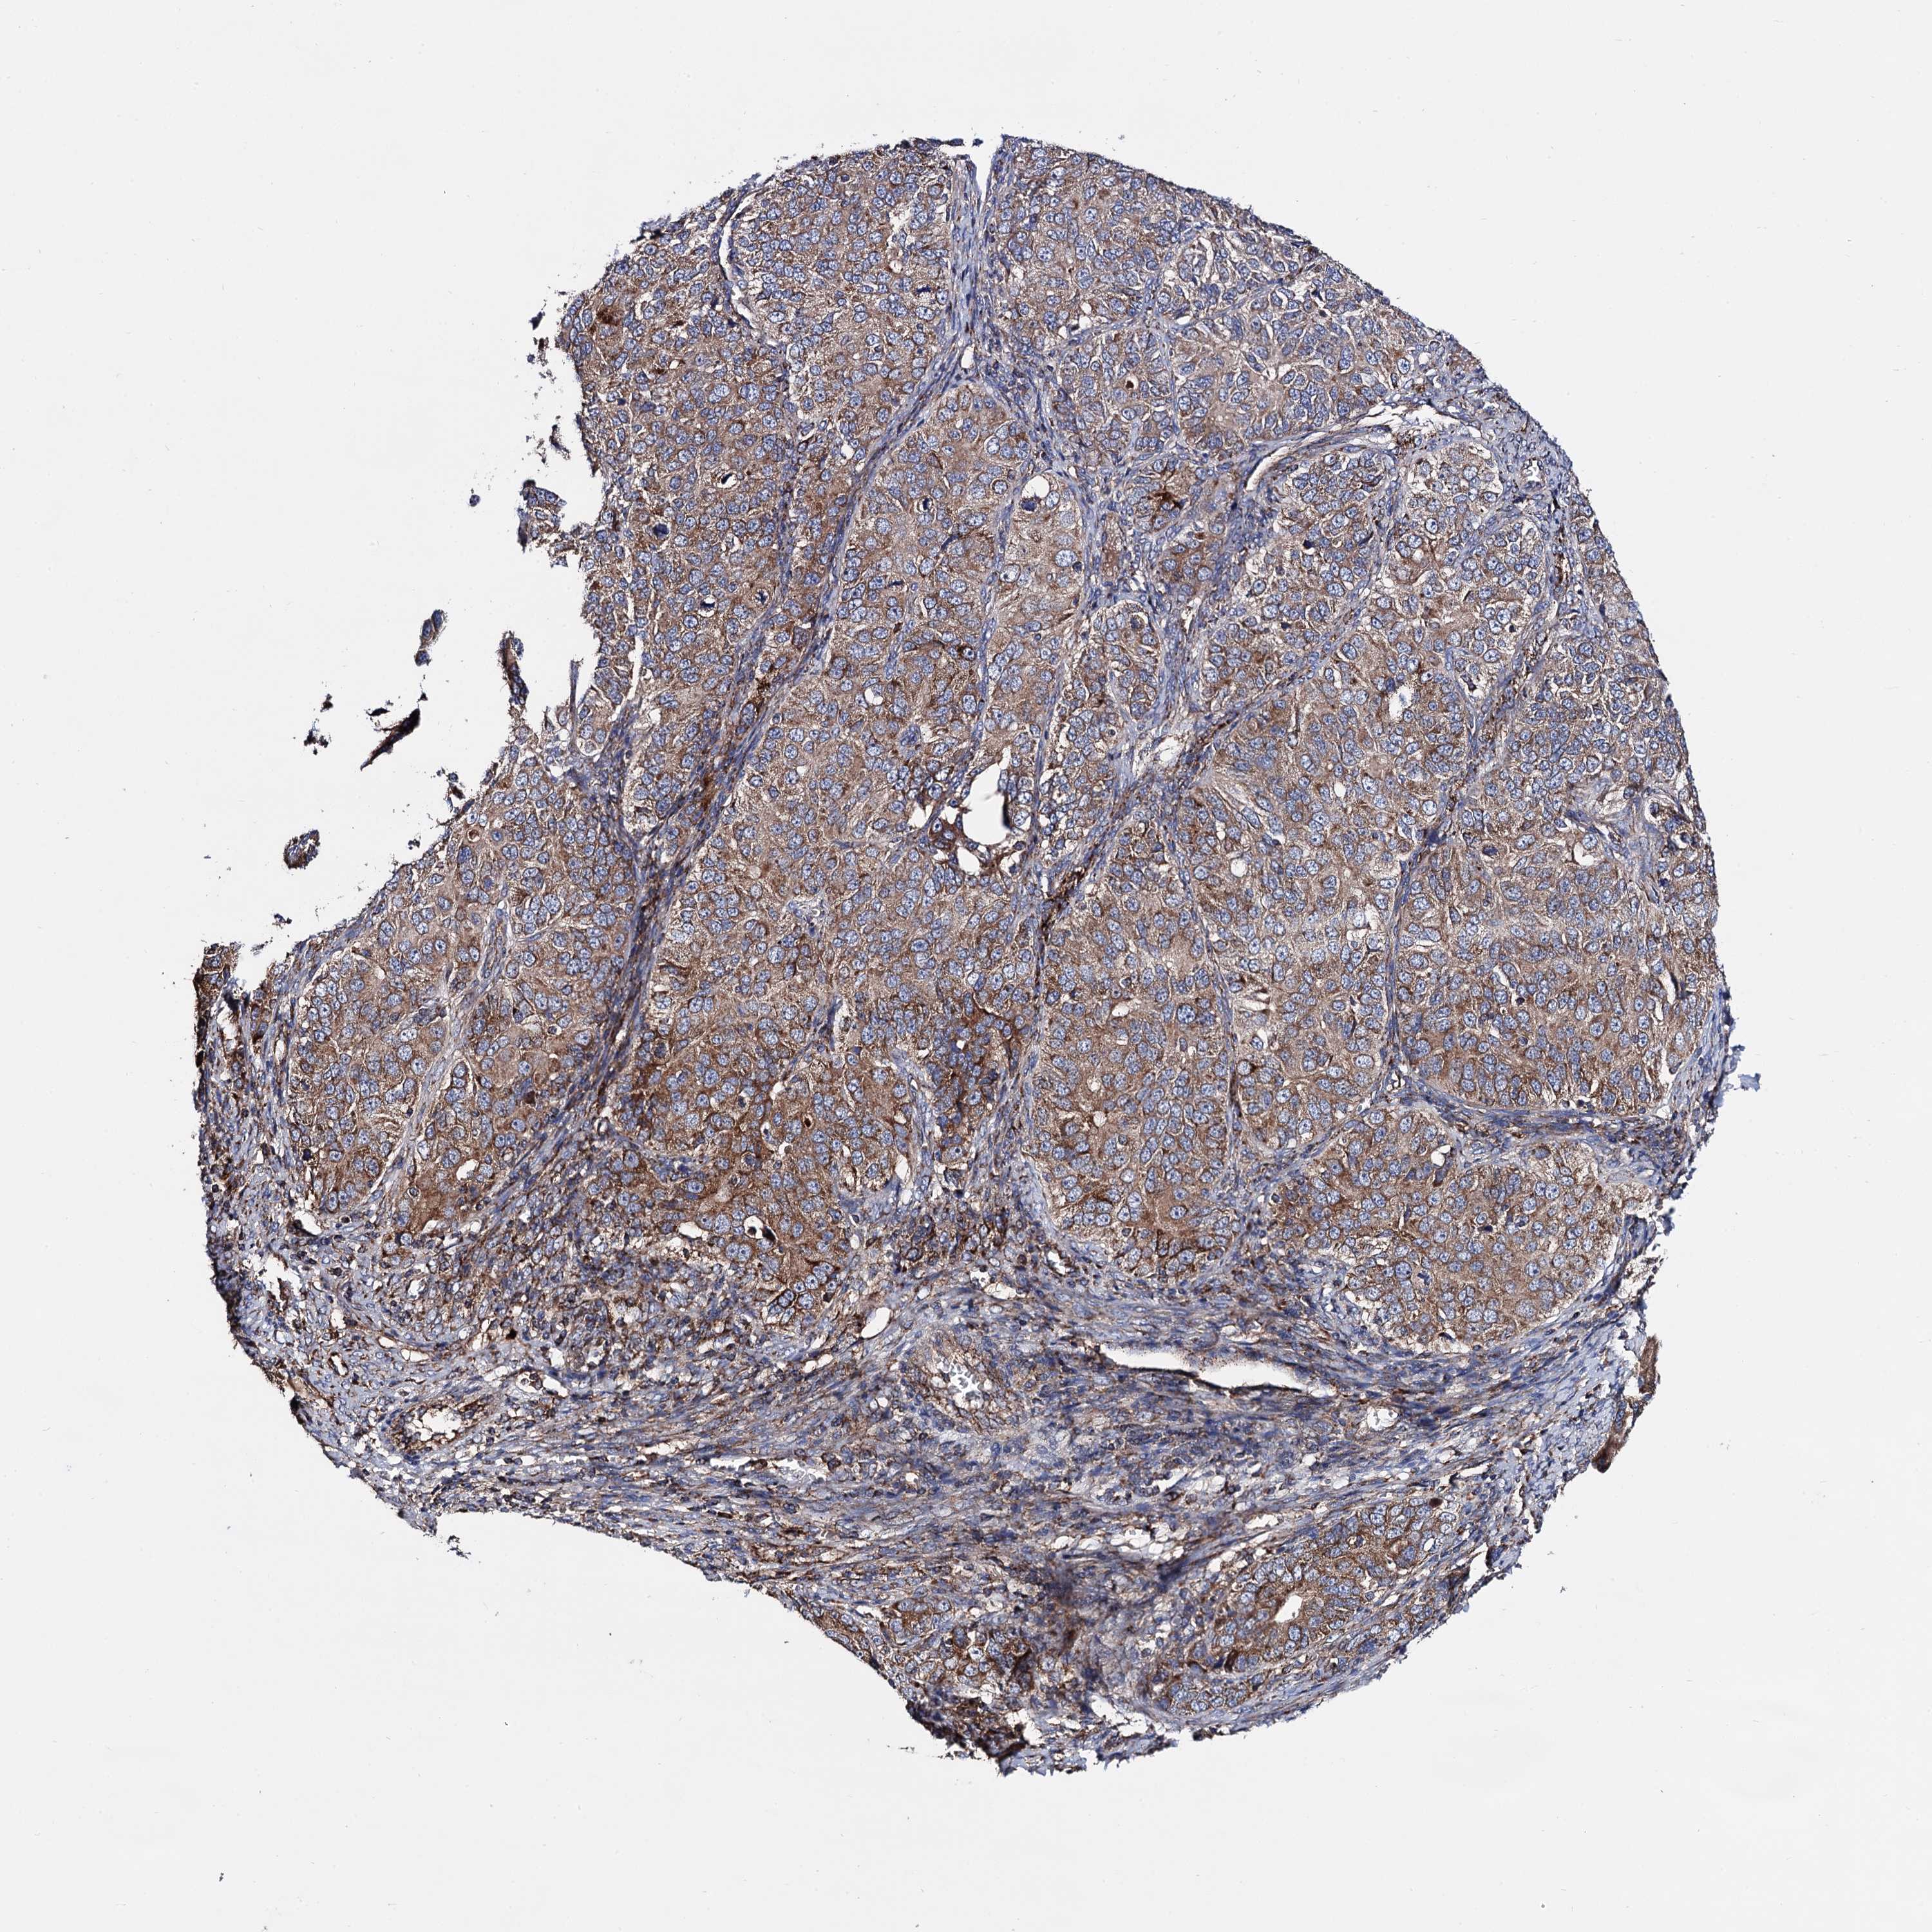

OVARIAN CANCER - Protein expressioni

A mouse-over function shows sample information and annotation data. Click on an image to view it in a full screen mode. Samples can be filtered based on level of antibody staining by selecting one or several of the following categories: high, medium, low and not detected. The assay and annotation is described here.

Note that samples used for immunohistochemistry by the Human Protein Atlas do not correspond to samples in the TCGA dataset.

Antibody stainingi

Antibody staining in the annotated cell types in the current human tissue is reported as not detected, low, medium, or high, based on conventional immunohistochemistry profiling in selected tissues. This score is based on the combination of the staining intensity and fraction of stained cells.

Each image is clickable and will lead to virtual microscopy that enables deeper exploration of all samples and also displays staining intensity scores, fraction scores and subcellular localization as well as patient and tissue information for each sample.

Antibody HPA040845

Staining

High

Medium

Low

Not detected

Intensity

Strong

Moderate

Weak

Negative

Quantity

>75%

75%-25%

<25%

None

Location

Nuclear

Cytoplasmic/membranous

Cytoplasmic/membranous,nuclear

Cystadenocarcinoma, serous, NOS

Carcinoma, endometroid

Cystadenocarcinoma, mucinous, NOS

Carcinoma, NOS